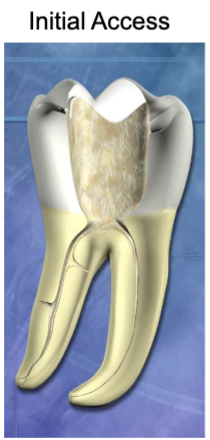

goals of access include:

locate ________

__________ access to canals

removal of ________ and _________

conservation of _______

all canals

straight-line

chamber roof; coronal pulp tissue

tooth structure